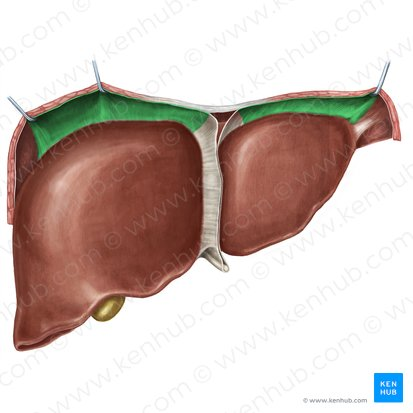

Right liver lobe

orange highlight

Left liver lobe

yellow highlight

Falciform ligament

Coronary ligament